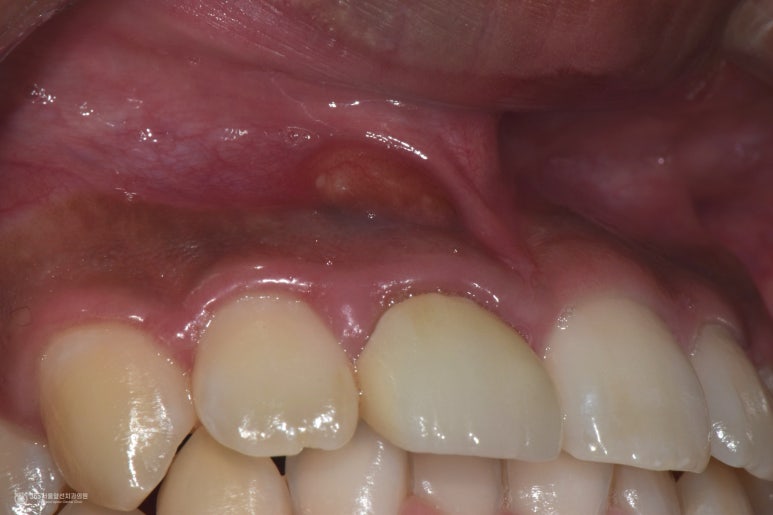

촬영일시 : 2024.10.15 또한 앞니 보철물도 새로 잘 만들어드렸습니다. 고름주머니도 소실되었고 통증도 사라졌습니다ㅎㅎ 오늘 소개해 드린 주안동치과추천 365서울앞선치과의원 치료 증례는 오래전 신경치료된 치아에 염증이 재발하여 재신경치료를 하여 치아를 살린 치료입니다. 재신경치료는 난이도가 높은 치료 술식에 해당하므로 전문가와 충분한 상의를 거친 후 치료를 받으시는 것이 중요하겠습니다 ㅎㅎ 앞으로도 좋은 치료 증례로 찾아뵙겠습니다. 감사합니다 ㅎㅎ [치료기간: 2024년 9월13일 ~2024년 10월15일] ※365서울앞선치과의원의 모든 포스팅은 각 진료과 의료진이 직접 작성합니다. 365서울앞선치과의원 블로그의 임상 케이스 게시물은 환자분께 의학적으로 정확하고 상세한 정보를 드리기 위해 각 진료과 의료진이 직접 작성하며, 모든 증례 사진은 본원 의료진이 직접 시술한 증례를 촬영한 것으로, 의료법 제23조, 제56조에 의거하며 환자분의 동의를 얻어 포스팅에 사용하였습니다. 또한 해당 케이스는 본 환자분의 치료 결과이며, 환자 상태에 따라 치료의 결과는 달라질 수 있습니다. |